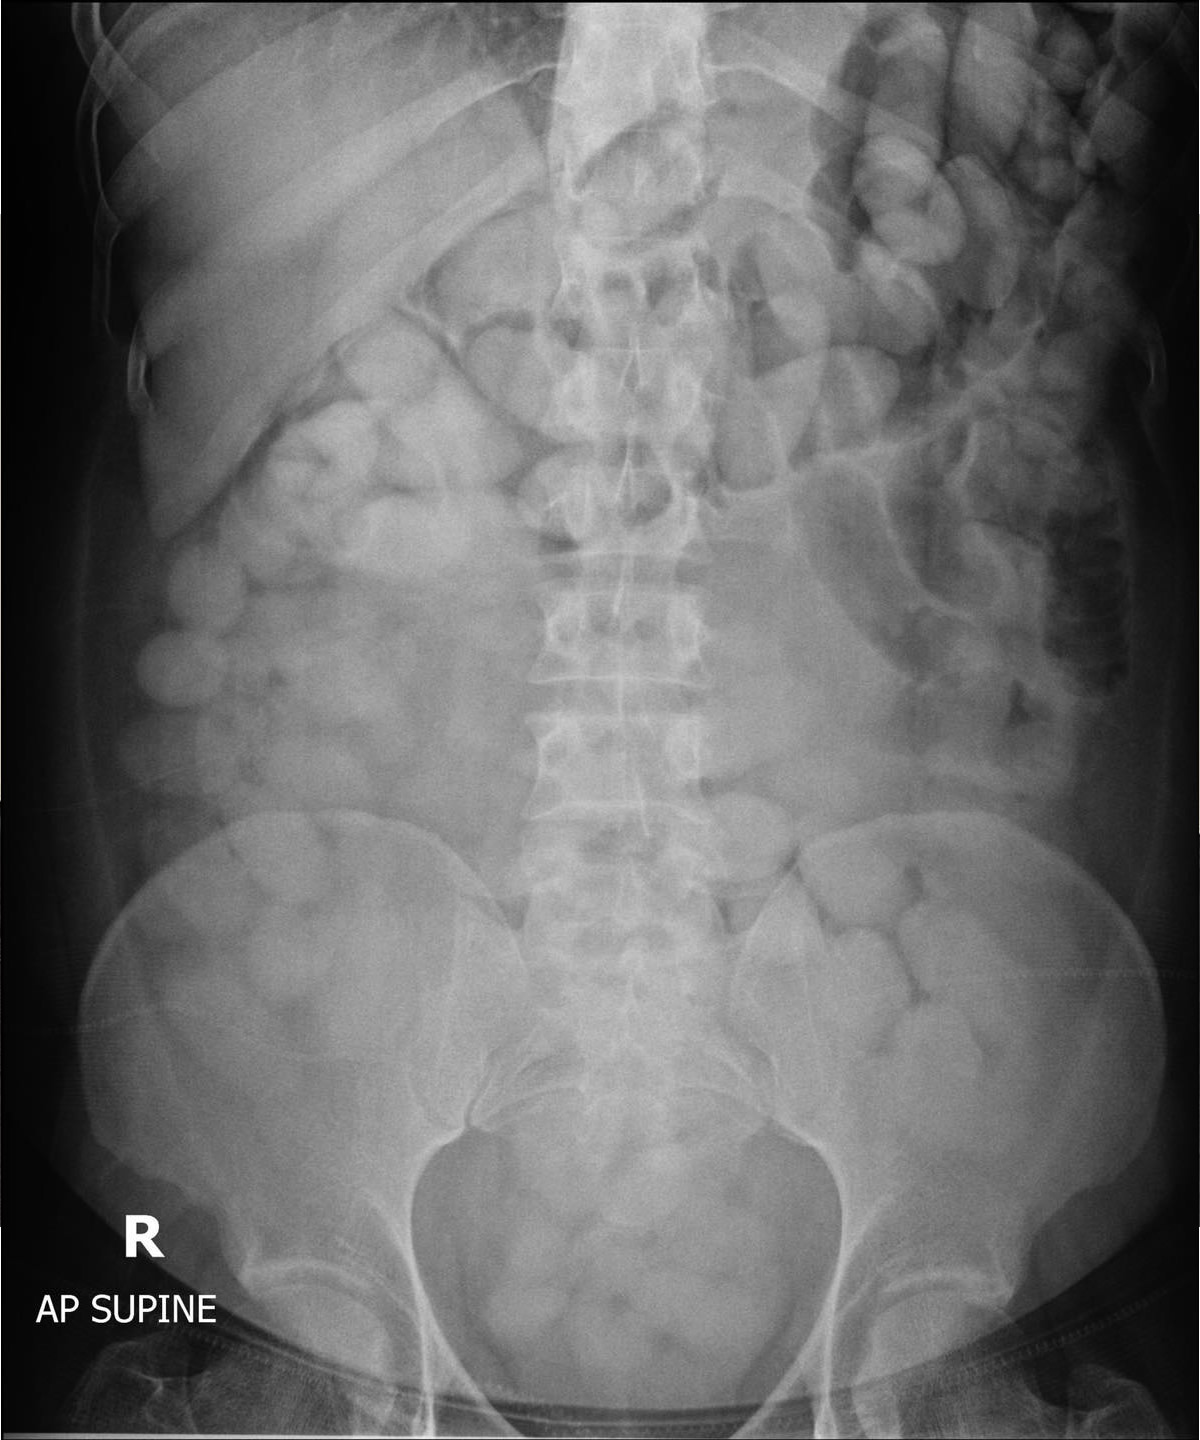

6月9日にプーケット空港で逮捕されたのは、エチオピア・ アディスアベバから到着した29歳の南アフリカ国籍の男で、コカインを飲み込む手口での密輸でした。タイ関税局によると、手荷物検査では何も見つかりませんでしたが、タラン病院に連れて行きレントゲン撮影を行ったところ、お腹の中に異物を発見。それが115個に分けられた総重量1.49キログラム(447万バーツ相当)のコカインでした。